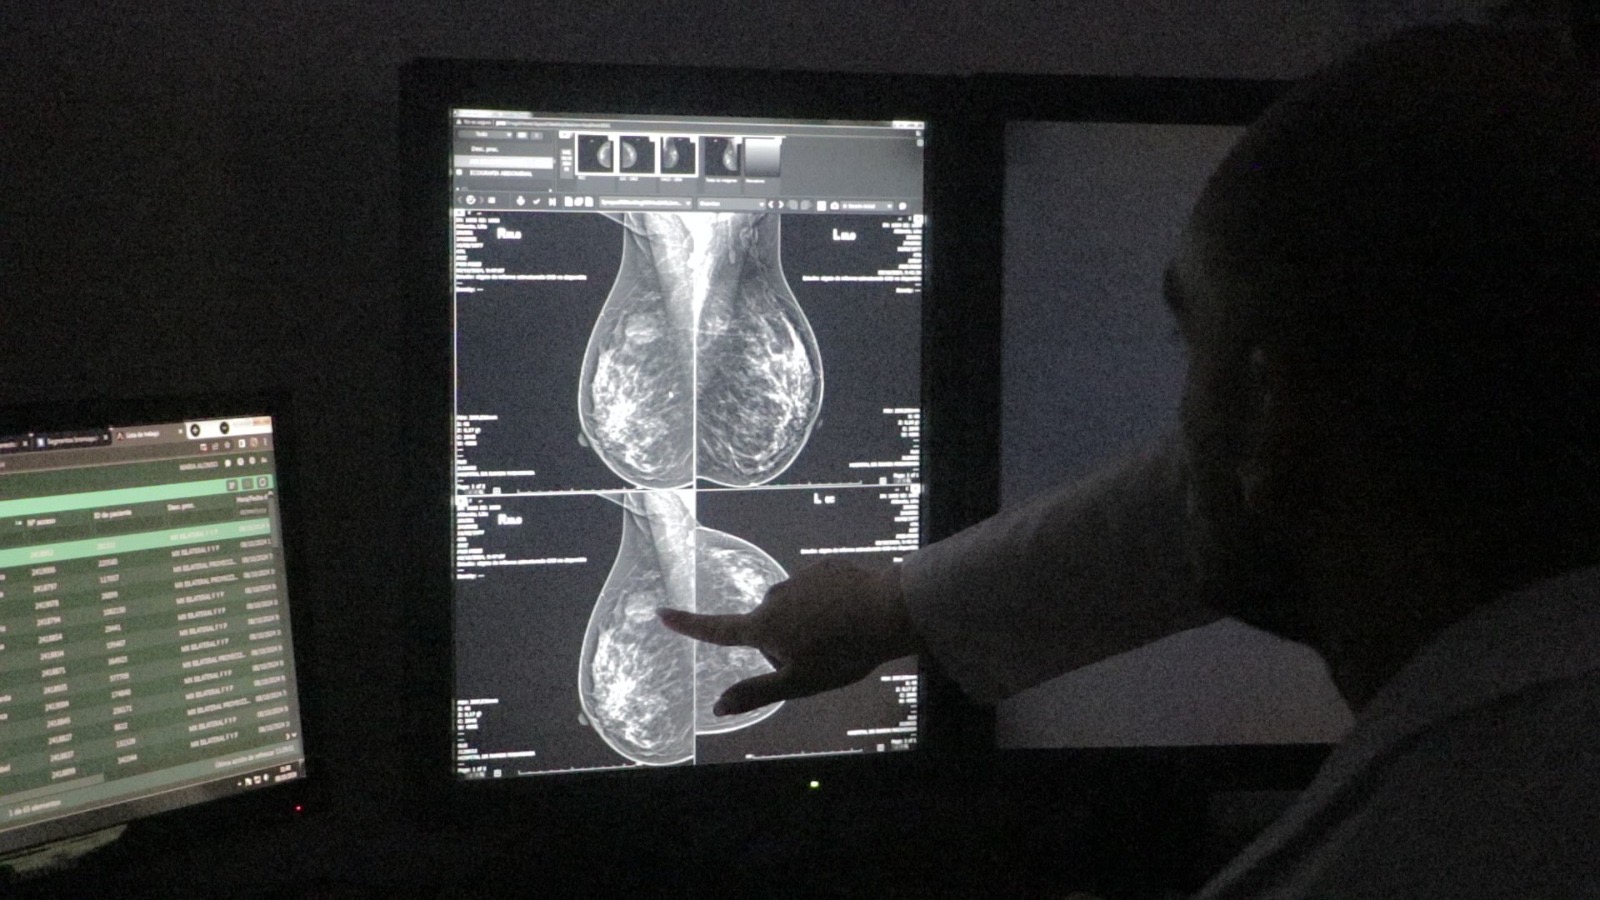

“Quiero decirles que hoy en día no es un diagnóstico grave. Hay cánceres que son curables y la gran mayoría son tratables. Lo importante es tener un diagnóstico temprano, mantener una interacción constante con el médico y confiar en las imágenes y estudios. Hemos evolucionado muchísimo en los tratamientos gracias a la investigación”.

Por último, Rabinovich alentó a las pacientes a confiar en los equipos médicos: “Anímense a hacerse los controles y, si ya han sido diagnosticadas, saquen los temores y confíen en los profesionales. El Instituto de Cáncer y el Hospital de Madariaga cuentan con profesionales brillantes. Confíen en ellos”.